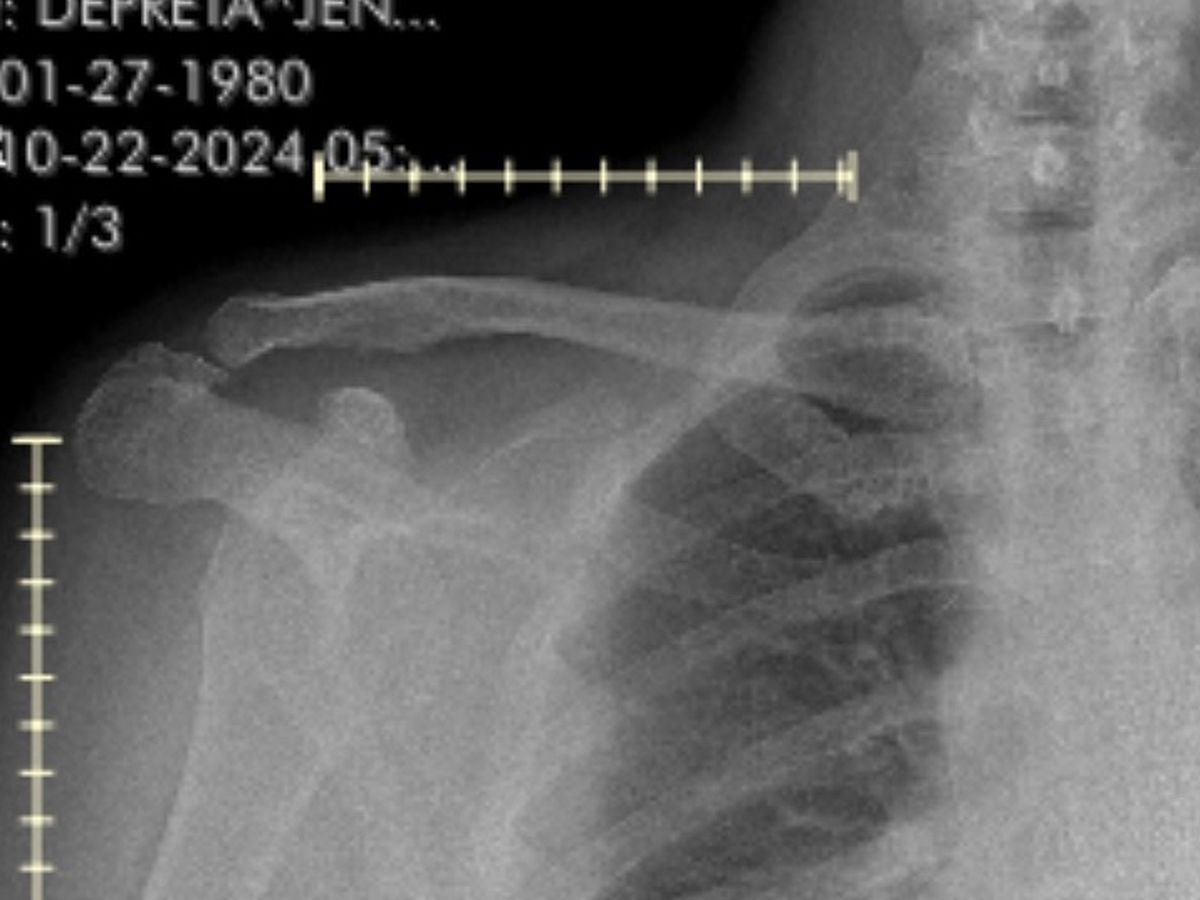

Jennifer is facing a challenging time as she navigates through the aftermath of a grand mal seizure that left her with bilateral dislocated shoulder and two broken humerus bones. As a mother of three Jennifer's ability to care for her family has been significantly impacted by this unforeseen medical emergency. This campaign has been launched to support Jennifer and her family during this difficult period. Any contribution, no matter how small, will make a difference in helping Jennifer get the medical treatment she needs and alleviating the financial burden that comes with such an unexpected health crisis. Your support and generosity will go a long way in assisting Jennifer on her road to recovery and ensuring that she can continue to be there for her children. Jennifer’s left shoulder, requires surgery further impacting her job as a hairstylist because of the length of recovery.